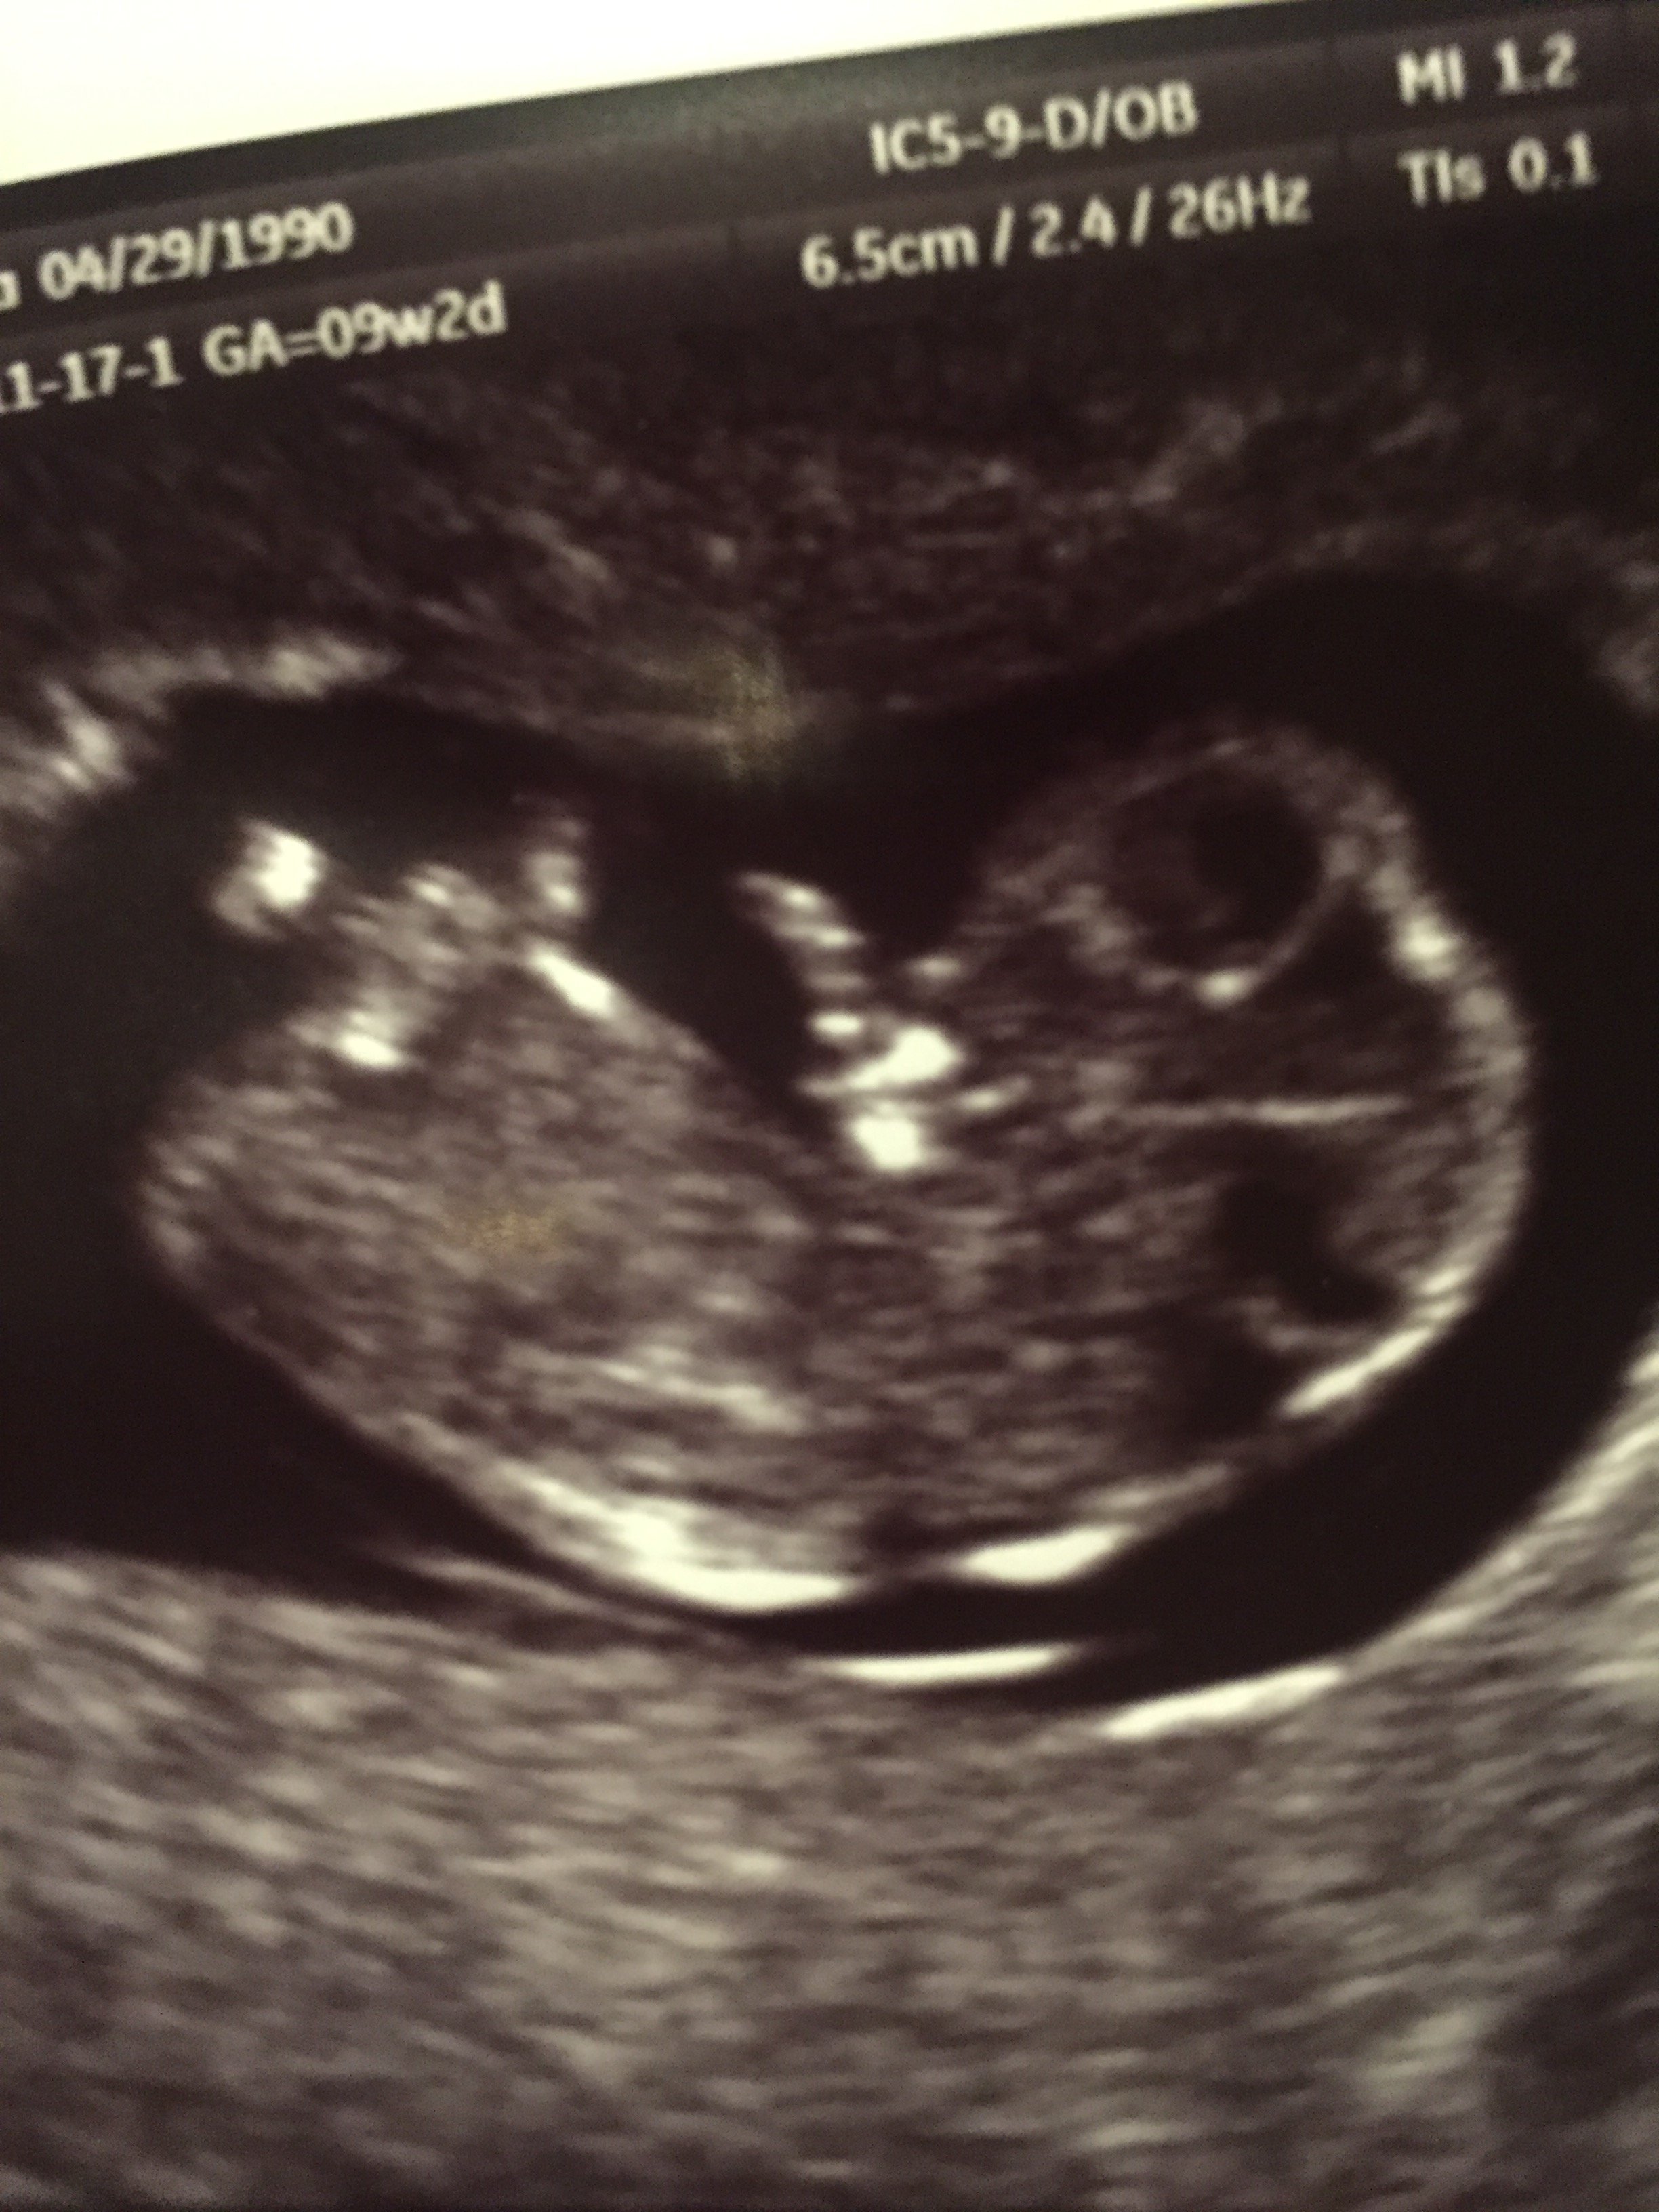

Ja również już po wizycie:):) krwiak się wchłonął :D więc odetchnęłam. Fasolka ma już 2,7 cm macha rączkami i nóżkami a nawet wkłada rączkę do buzi :D cudny widok! 10tc (9+2 z OM a z badań 9+4) prenatalne mam na 4 kwietnia. Pani doktor obstawia chłopczyka bo jest duży wyrostek płciowy ale 100% nie daje.